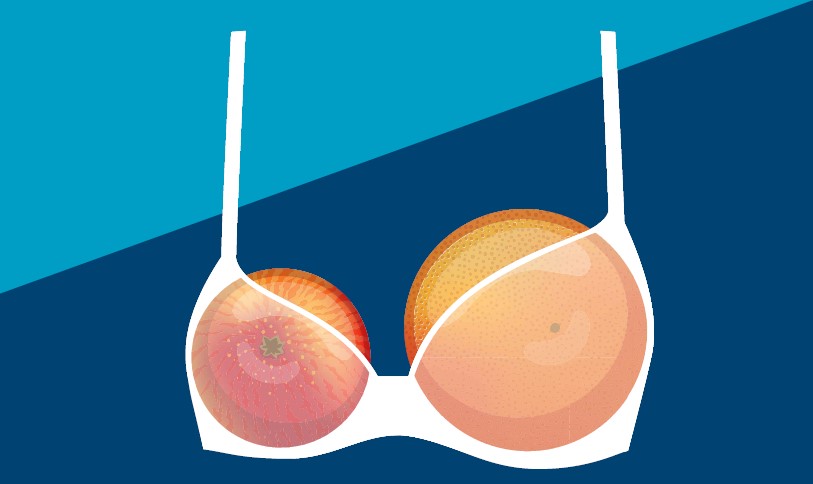

Zurück zur Symmetrie: mit einer Ausgleichsform, die sich perfekt an Ihren Körper anpasst

Ungleiche Brüste ... nicht gerade ein leichtes Thema, aber viele Frauen leiden nach einer Brustkrebstherapie darunter. Brustasymmetrie tritt meist unmittelbar nach dem Behandlungs- und Genesungsprozess auf. Neben der emotionalen Belastung können ungleichmäßige Brüste auch zu körperlichen Schwierigkeiten führen, wenn diese stark ausgeprägt sind. Ein etwaiger Gewichtsunterschied kann möglicherweise zu einer falschen Körperhaltung führen, was wiederum Verspannungen in Nacken, Schulter und Rücken zur Folge hat..

Brustasymmetrie tritt meist unmittelbar nach dem Behandlungs- und Genesungsprozess auf und kann die Lebensqualität stark beeinträchtigen. Neben der emotionalen Belastung können ungleichmäßige Brüste auch zu körperlichen Schwierigkeiten führen, wenn diese stark ausgeprägt sind. Ein etwaiger Gewichtsunterschied kann möglicherweise zu einer falschen Körperhaltung führen, was wiederum Verspannungen in Nacken, Schulter und Rücken zur Folge hat. Viele Frauen empfinden Irritationen und Unwohlsein, weil ihr bisheriger BH nicht mehr richtig sitzt.

Eine Ausgleichform kann eine großartige nicht-invasive Lösung sein, um die Brustsymmetrie wiederherzustellen und das Selbstvertrauen zu stärken.

| ohne Ausgleichsform | → | mit Balance Adapt Air |

Ausgleichsformen sind Silikonformen, die Sie in Ihrem BH tragen, um so die Brustsymmetrie wiederherzustellen. Aufgrund vieler verschiedener Formen und Größen empfehlen wir Ihnen für die optimale Anpassung den Sanitätsfachhandel aufzusuchen. Unsere Ausgleichsformen werden aus hochwertigem Silikon hergestellt, dass für eine außergwöhnlich natürliche Passform und Gefühl auf der Haut sorgt. Zusätzlich nimmt unsere Comfort+ Technologie die Körperwärme auf, speichert sie und gibt sie wieder ab, um Schwankungen der Körpertemperatur zu regulieren und auszugleichen - für einen ultimativen Komfort den ganzen Tag lang.

Das Tragen einer Ausgleichsform ist bequem und einfach. Sie können diese in jeden gut sitzenden BH einlegen. Wir empfehlen Ihnen jedoch, die Ausgleichsform in Verbindung mit einem Spezial-BH von Amoena zu tragen, da deren spezielle Beschaffenheit (höherer Schnitt an der Vorderseite und an den Seiten) einen sicheren Sitz der Ausgleichsform gewährleistet..